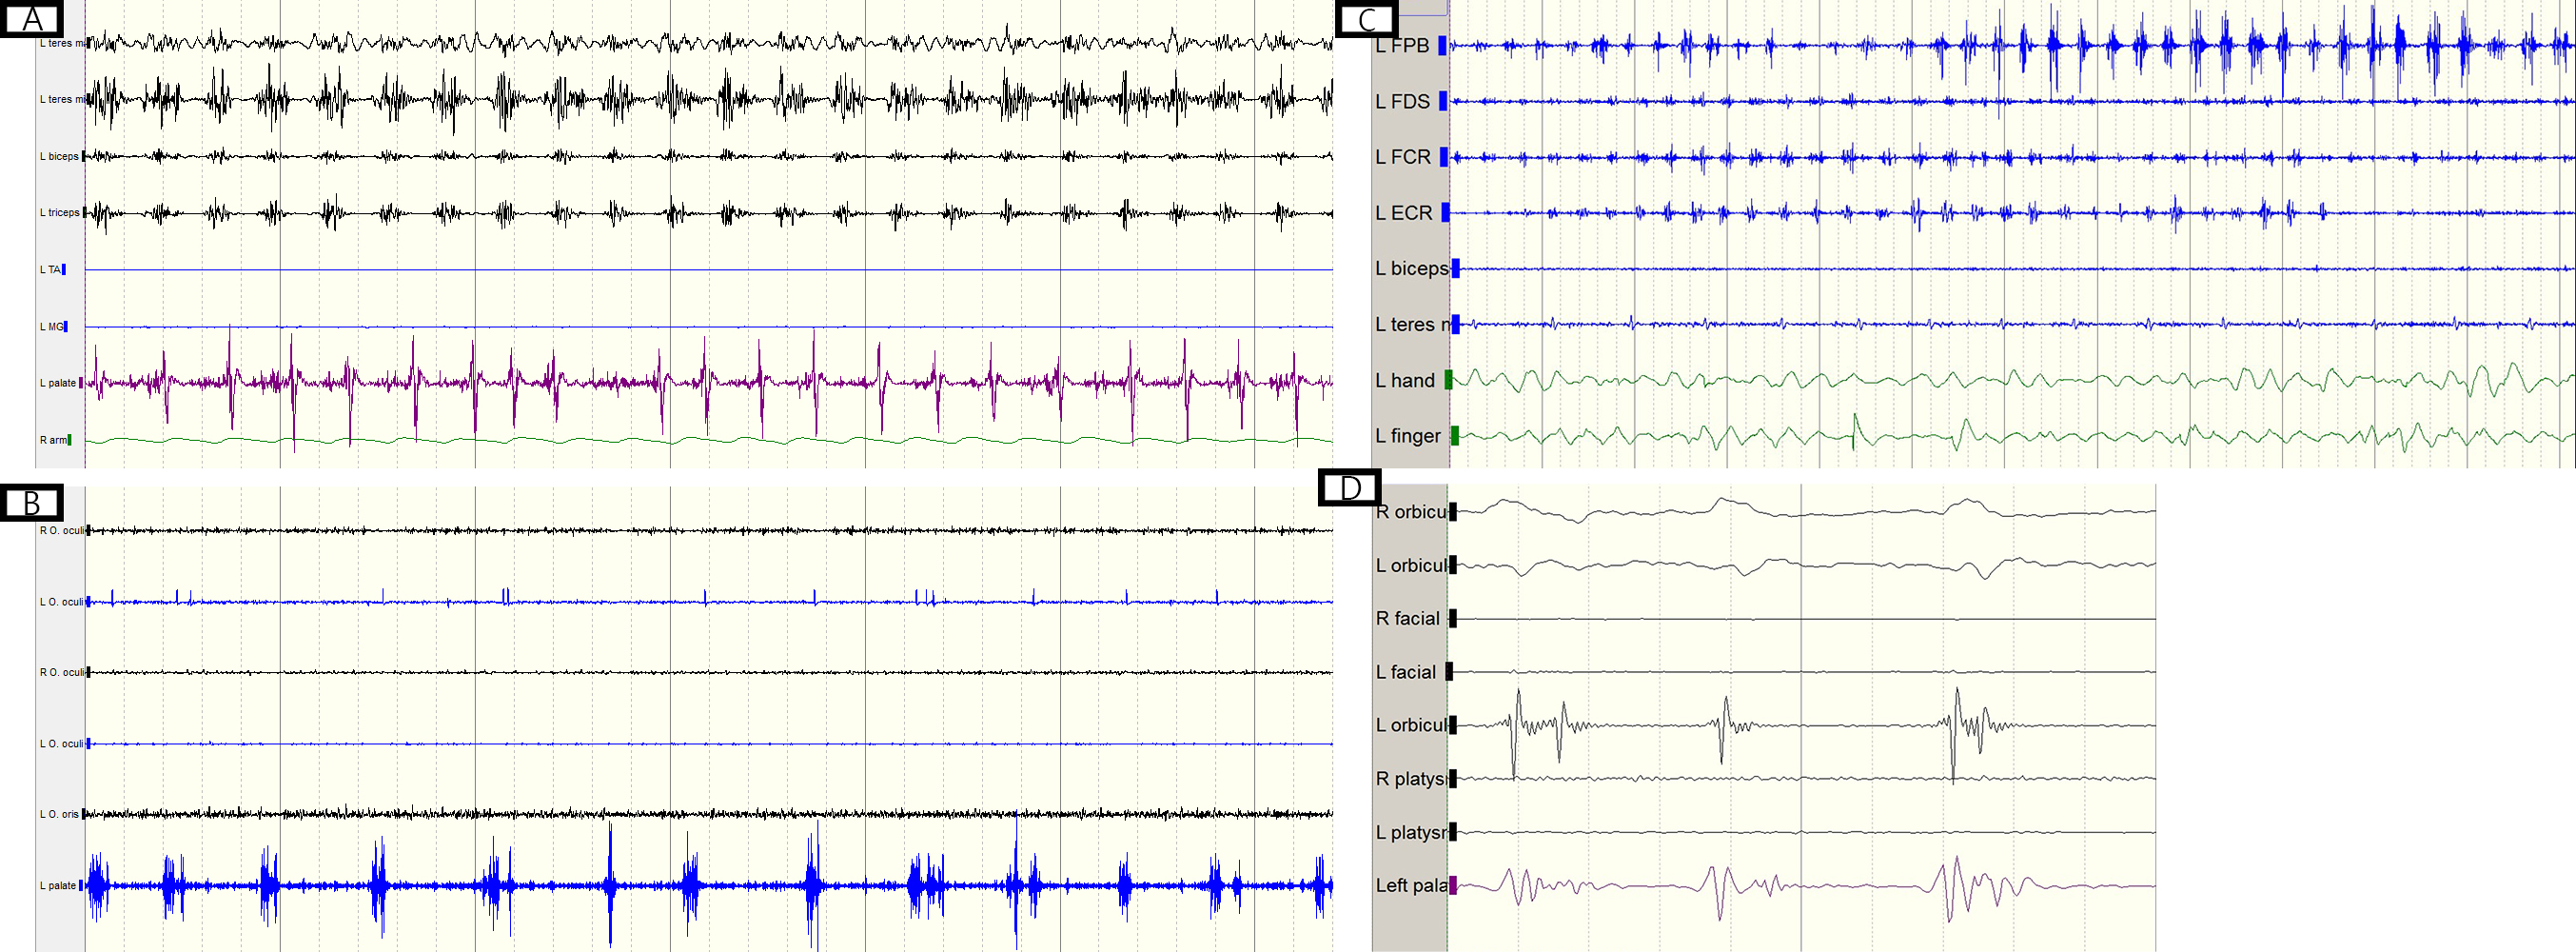

Electrophysiologically, all patients exhibited well-formed and 150-200ms bursting activity in all sampled muscles, including those of the palate, face, and upper and lower limbs. There was a periodic wax-and-wane pattern of the bursting amplitudes at a fixed frequency ranging from 1 to 3 Hz [figure]. The time lag from palatal to facial muscle bursting was 25ms, and from palatal to shoulder muscle bursting was 50ms.

Conclusion: Contralateral cerebellar ataxia instead of palatal tremor is the most common sign of hypertrophic olivary degeneration. There are common electrophysiological features of 150-200ms duration, well-forming bursting pattern, and wax-and-wane amplitudes across all involved muscles. Our finding supports the hypothesis of dual mechanism: oscillations originating in the hypertrophic inferior olive and amplified by the cerebellum cortex.

Figure